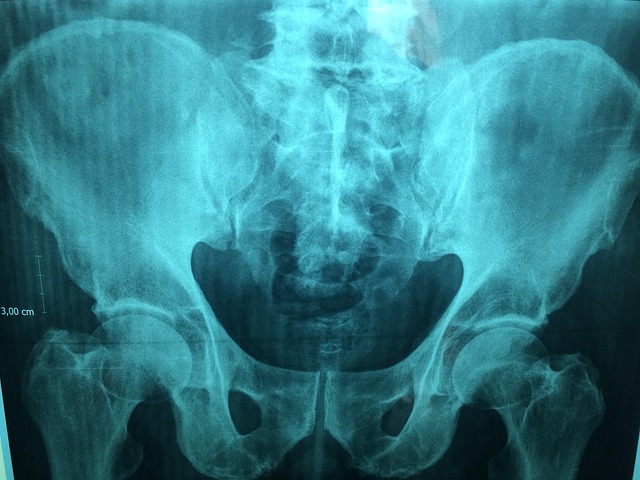

| PSA(전립선특이항원) 검사 | 전립선암 조기발견 | 50세 이상 |

| 복부 초음파 | 지방간, 췌장, 담낭 이상 여부 확인 | 40대 후반 이상 |